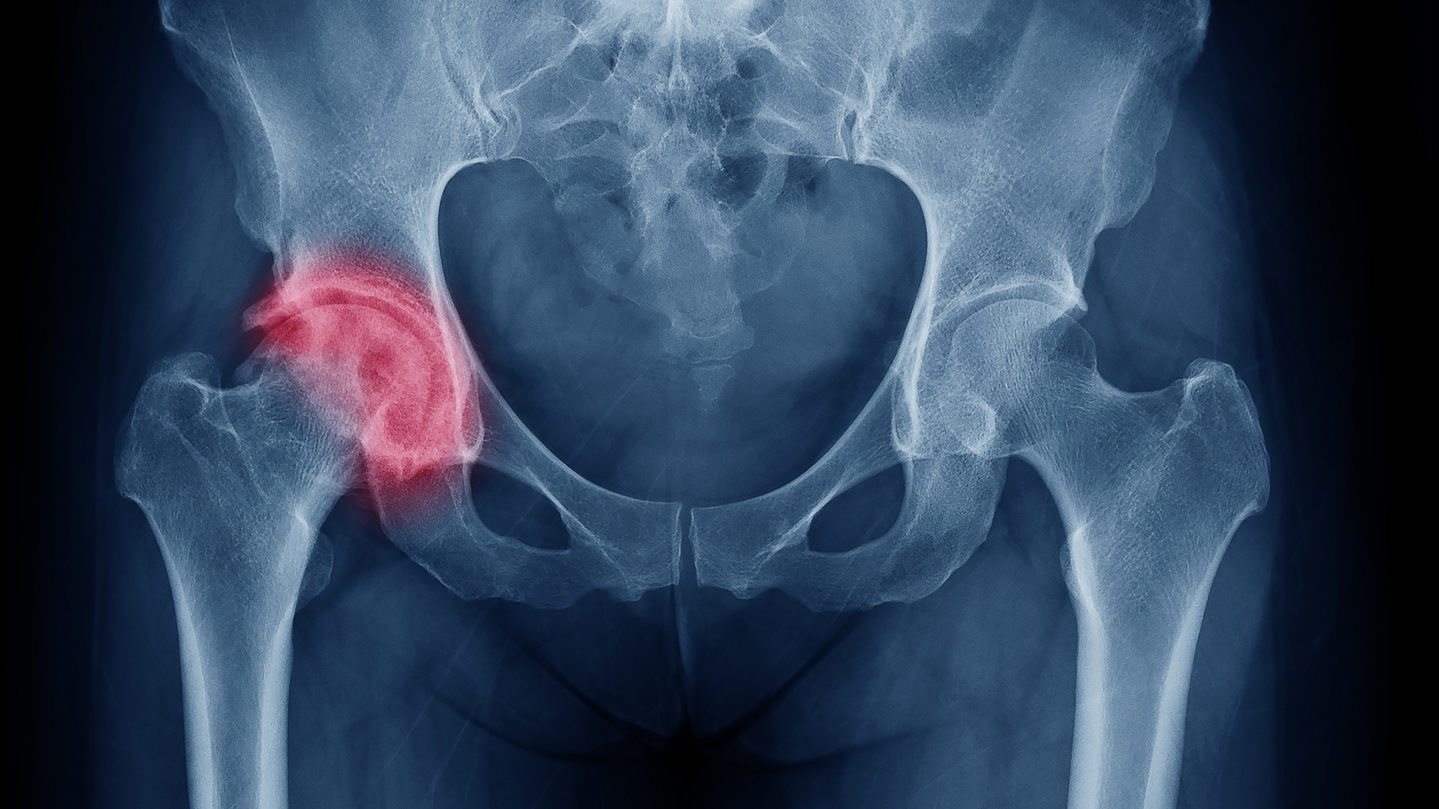

Gençlerde Kalça Kırığı Neden Olur?

Araç kazaları, düşmeler veya spor yaralanmaları gibi büyük travmalar yol açabilir. Ekstrem sporlarla uğraşan gençlerde, ani ve güçlü darbeler neden olabilir. Kemik gelişim bozuklukları veya genetik olarak zayıf kemik yapısı, riski artırabilir. Osteoporoz gibi kemik zayıflığına neden olan hastalıklar genç yaşta nadir olsa da, bazı durumlarda kırığa yol açabilir.

Gençlerde sürekli tekrarlanan hareketler, stres kırığı olarak bilinen küçük çatlaklara neden olur. Yetersiz kalsiyum veya D vitamini alımı kemik sağlığını olumsuz etkileyerek gençlerde kalça kırığı riskini artırabilir. Hızlı büyüme dönemlerinde hormonal dengesizlikler kemik gücünü zayıflatabilir. Bu nedenler kalça kırığına yol açabilecek çeşitli faktörlerdir ve önlem alınması önemlidir.